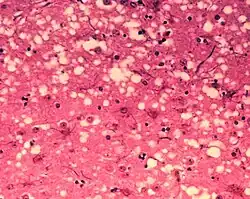

El neuropilo está formado por sectores anatómicos y fisiológicos dentro de la sustancia gris. Cada uno contiene: varios cuerpos de neuronas, las sinapsis y la glía que se agrupan con alta densidad en la materia gris de los tejidos cerebrales y medulares, donde ocurre el almacenamiento y procesamiento de la información.

Cada Neuropilo contiene varios cuerpos (somas) de neuronas. Se compone además de un «ovillo» denso de terminales de axones, de dendritas y de células gliales (astrocitos, microglía y oligodendrocitos). También comprende las conexiones o sinapsis formadas entre las ramificaciones axónicas presinápticas y las dendríticas postsinápticas.[3] [4]